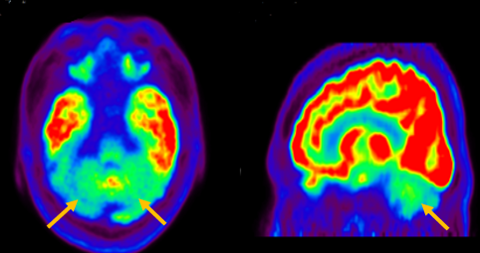

다계통 위축이란 뇌의 다양한 계통에서 위축이 발생하는 것을 의미합니다. 파킨슨 증상이 있으면서 질병 초기에 소변 장애나 기립성 저혈압으로 인한 어지러움이 두드러지게 나타나는 경우, 보행 시 비틀거림이나 구음 장애와 같은 소뇌 위축에 따른 운동 실조 증상이 나타나는 경우, 꿈에서 하는 행동을 수면 중에 보이는 렘수면 행동 장애가 동반되는 경우 다계통 위축을 의심합니다. 다계통 위축은 파킨슨병과 달리 안정 시 떨림이 잘 보이지 않고, 증상이 대칭적인 경우가 많으며, 진행이 빠르며, 레보도파와 같은 항파킨슨 약제에 잘 반응하지 않습니다. 다계통 위축은 뇌 자기공명영상(MRI)에서 교뇌에 십자 모양의 고음영이 나타날 수 있는데, 이를 십자무늬 빵(hot cross bun) 징후라고 합니다. 또한 초기에서는 뇌 자기공명영상(MRI)이 정상으로 보이더라도 뇌포도당 양전자 단층촬영(PET)에서는 소뇌 또는 기저핵의 대사 기능이 저하된 상태가 관찰될 수 있습니다. 이러한 영상 소견은 특징적인 임상 증상과 함께 진단에 참고할 수 있습니다.

[다계통위축 환자의 뇌포도당 양전자 단층 촬영에서 확인되는 소뇌의 대사 기능 저하]